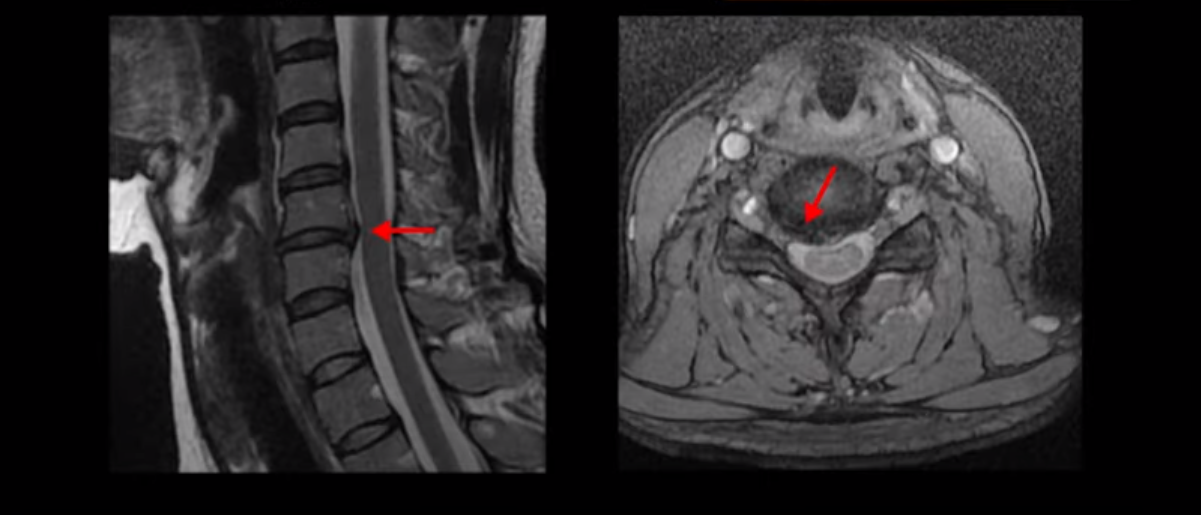

이 환자분 X-ray, MRI 보고 간단히 설명 드린 후 왜 목디스크 치료가 허리디스크에 비해 훨씬 더 쉬운지 자세히 설명 드리겠습니다.

이런 목 형태를 가지면 항상 목이 뻐근하고 담이 걸린 것처럼 아프기 쉽습니다. 그리고 이런 거북목의 형태는 목에 엄청난 부담을 주기 때문에 디스크가 퇴행되면서 언젠가는 찢어지기 쉽습니다. 그래서 결국 5번 6번 목디스크가 찢어지면서 오른쪽으로 밀려나옵니다.

그래서 심한 목통증과 함께 오른쪽 어깨, 오른팔과 손마디가 다 저리고 아픕니다. 아예 목이 안 돌아가고 움직이지 못할 정도로 아파서 빠른 치료를 위해 바로 입원치료를 받으셨는데요. 이분은 목디스크 평균 치료기간인 2주보다 짧은 딱 일주일 입원치료를 받으셨습니다. 어떻게 신경이 눌려 있는 목디스크가 1-2주 만에 좋아질 수 있을까요. 왜 우리는 목디스크가 허리에 비해 훨씬 더 치료가 쉽고 빠르다고 얘기하는 걸까요?

이 환자분도 아까 X-ray에서 보여드렸듯이 아주 심한 일자목, 거북목이 있고 그 결과로 목의 거의 모든 마디가 다 퇴행이 진행되어 있죠. 즉 거북목은 모든 목질환, 특히 목디스크, 목협착증의 어머니 질환이며 그래서 목디스크를 치료하기 위해서는 반드시 거북목 때문에 짧아지고 뭉치고 굳고 뒤틀린 목 주변 근육들을 잘 치료해줘야 합니다.